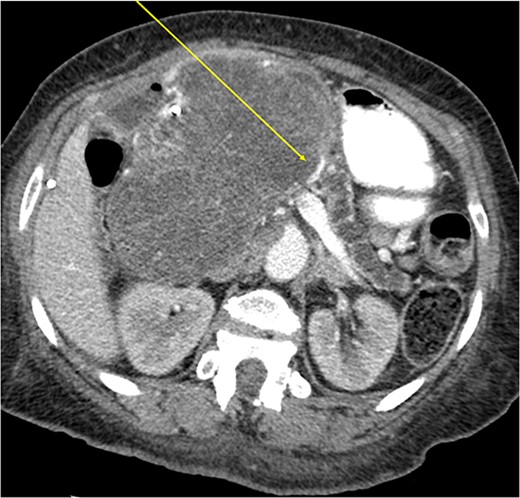

Another abdominal CT was performed redemonstrating the large heterogenous mixed attenuating mass within the right abdomen measuring 14.0 × 10.0 × 13.0 cm likely originating from the pancreatic head with resultant displacement of the PTC anteriorly and to the right with extensive pancreatic ductal dilation (Figs 2 and 3).

Coronal CT showing a large heterogeneous mass in the pancreatic head with typical honeycomb feature.

Mass effect to abdominal viscera from the 14 × 10 × 13 cm pancreatic head mass.

The mass extended up into the base of the liver, effaced the portal and superior mesenteric veins (SMV) (Fig. 4), and displaced the hepatic and superior mesenteric arteries.